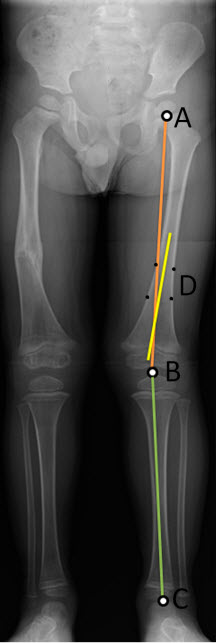

Μέτρηση γωνιών ισχίου-γόνατου-αστραγάλουΑριθμός θέματος: 1425412403399

- Κάντε κλικ σε τρία σημεία στο περίγραμμα της οστεοποιημένης κεφαλής του μηριαίου. (Το κέντρο εμφανίζεται ως A στο διάγραμμα.)

- Κάντε κλικ στην περιφερική επίφυση του μηριαίου (Β στο διάγραμμα).

- Κάντε κλικ στην τροχιλία αστραγάλου (C στο διάγραμμα).

Σχηματίζεται μια γραμμή ανάμεσα στην επίφυση του μηριαίου και την τροχιλία αστραγάλου. Επίσης σχηματίζεται μια γραμμή που επισημαίνει τη γωνία ανάμεσα στις δύο γραμμές.

Οι γραμμές στην εφαρμογή εμφανίζονται σύμφωνα με τις προεπιλογές χρωμάτων του συστήματος. Το διάγραμμα χρησιμοποιεί διαφορετικά χρώματα προς αποφυγή αμφισημίας.